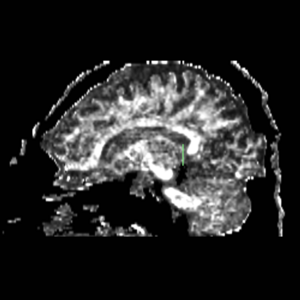

Figure 5. Sagittal view of the fornix, located centrally in the brain

ROI 1 was drawn on the sagittal slice, 5 slices superior to the anterior commisure (Fig. 8 & 10). ROI 2 was drawn on a coronal slice where the crux of the fornix was present. It was not always the same slice for both sides (Fig. 9 & 11).

Figure 8. Axial View of ROI 1

Figure 9. Coronal View of ROI 2 (left=11, right=13)

Figure 10. Sagittal View of Fornix, ROI 1 (both left and right)

Figure 11. Sagittal View of Fornix, ROI 2 (right)